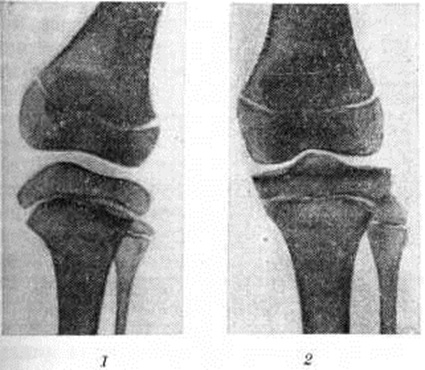

Моркио болезньМоркио болезнь (L. Morquio, уругвайский педиатр, 1867—1935; синонимы: Мукополисахаридоз тип IV, синдром Моркио — Брейлсфорда, множественный энхондральный дизостоз, деформирующая остеохондродистрофия) — наследственное заболевание соединительной ткани из группы мукополисахаридозов, характеризующееся множественными поражениями скелета, низким ростом, кератансульфатурией. Заболевание впервые описали в 1929 год независимо друг от друга Моркио и Брейлсфорд (J. F. Brailsford). До 1959 год к Моркио болезнь относили различные множественные поражения скелета, в том числе спондилоэпифизарную дисплазию, множественную эпифизарную дисплазию и другие В самостоятельную нозологический форму Моркио болезнь выделена после обнаружения специфического биохимический признака — наличия в моче мукополисахаридов. Частота Моркио болезнь примерно 1 : 40 000 среди новорожденных. Этиология и патогенез. Тип наследования — аутосомно-рецессивный. Патогенез связан с нарушением катаболизма кислых гликозамингликанов (мукополисахаридов) вследствие дефицита фермента — хондроитинсульфата-N-ацетил-гексозоаминсульфатсульфатазы. Клиническая картина. Первые симптомы появляются к концу первого — началу второго года жизни. Наблюдается гротескность черт лица, гипертелоризм (смотри полный свод знаний Дизостоз), седловидный нос, мегалоглоссия, мышечная слабость, отставание в двигательном развитии. Отмечается диффузная гипотрофия и дряблость мышц, изменение походки от лёгкой хромоты до утиной. К 3—4 годам формируются грубые костно-суставные деформации грудной клетки (куриная, бочкообразная, килеобразная), позвоночника (сколиоз и кифосколиоз), вальгусная деформация конечностей (рисунок 1). Замедляется темп роста, шея и туловище — короткие. К 7 —10 годам у некоторых детей появляются боли в конечностях, возникают контрактуры в локтевых, плечевых, коленных суставах. Миопатический симптомокомплекс нарастает; дети жалуются на слабость, утомляемость в состоянии покоя, снижение мышечной силы. Определяются признаки внутричерепной гипертензии (смотри полный свод знаний Гипертензивный синдром), вегетативная лабильность, повышение сухожильных рефлексов вследствие постепенного развития центральных парезов и параличей (смотри полный свод знаний Параличи, парезы). Психическое развитие, как правило, нормальное. При осмотре глазного дна выявляется атрофия диска зрительного нерва (смотри полный свод знаний). Диагноз устанавливается на основании клинические, картины, биохимический исследования мочи и рентгенологическое данных. В моче обнаруживается избыточная экскреция общего количества кислых гликозамингликанов, в частности кератансульфата. При рентгенологическое исследовании длинных и коротких трубчатых костей наблюдается нарушение роста эпифизов костей, проявляющееся в их уплощении, расширении и уменьшении высоты (рисунок 2) при отсутствии существенного торможения роста в эпифизарных хрящах. При рентгенографии позвоночника, как правило, обнаруживается заметное уплощение и расширение тел позвонков от CII до Lv — платибрахиспондилия (рисунок 3), чем и объясняется характерное укорочение туловища и необычно короткая шея при Моркио болезнь; межпозвоночные диски при этом мало изменены или не изменены вовсе. Переднезадний размер грудной клетки увеличен, межрёберные промежутки сужены, грудина дугообразно деформирована. Все эти изменения выявляются при обзорной (желательно телевизионной) рентгеноскопии с последующей обязательной рентгенографией тех отделов скелета, в которых обнаруживаются наиболее выраженные изменения. Дифференциальный диагноз следует проводить с другими типами мукополисахаридозов (смотри полный свод знаний), несовершенным остеогенезом (смотри полный свод знаний Остеогенез несовершенный), спондилоэпифизарными и метафизарными дисплазиями, витамин D-резистентным рахитом (смотри полный свод знаний Фосфат-диабет), почечным рахитом (смотри полный свод знаний Остеопатия нефрогенная), врождённым сифилисом (смотри полный свод знаний), гипотиреозом (смотри полный свод знаний). Лечение. Лечению подлежат больные с легкоустранимыми или стойкими деформациями конечностей, контрактурами, анкилозом суставов в порочном положении, вывихами и подвывихами в суставах, приводящими к нарушениям формы и функции конечностей. Лечение может быть консервативное и оперативное. Выбор метода лечения зависит от тяжести заболевания, возраста и общего состояния больного. |